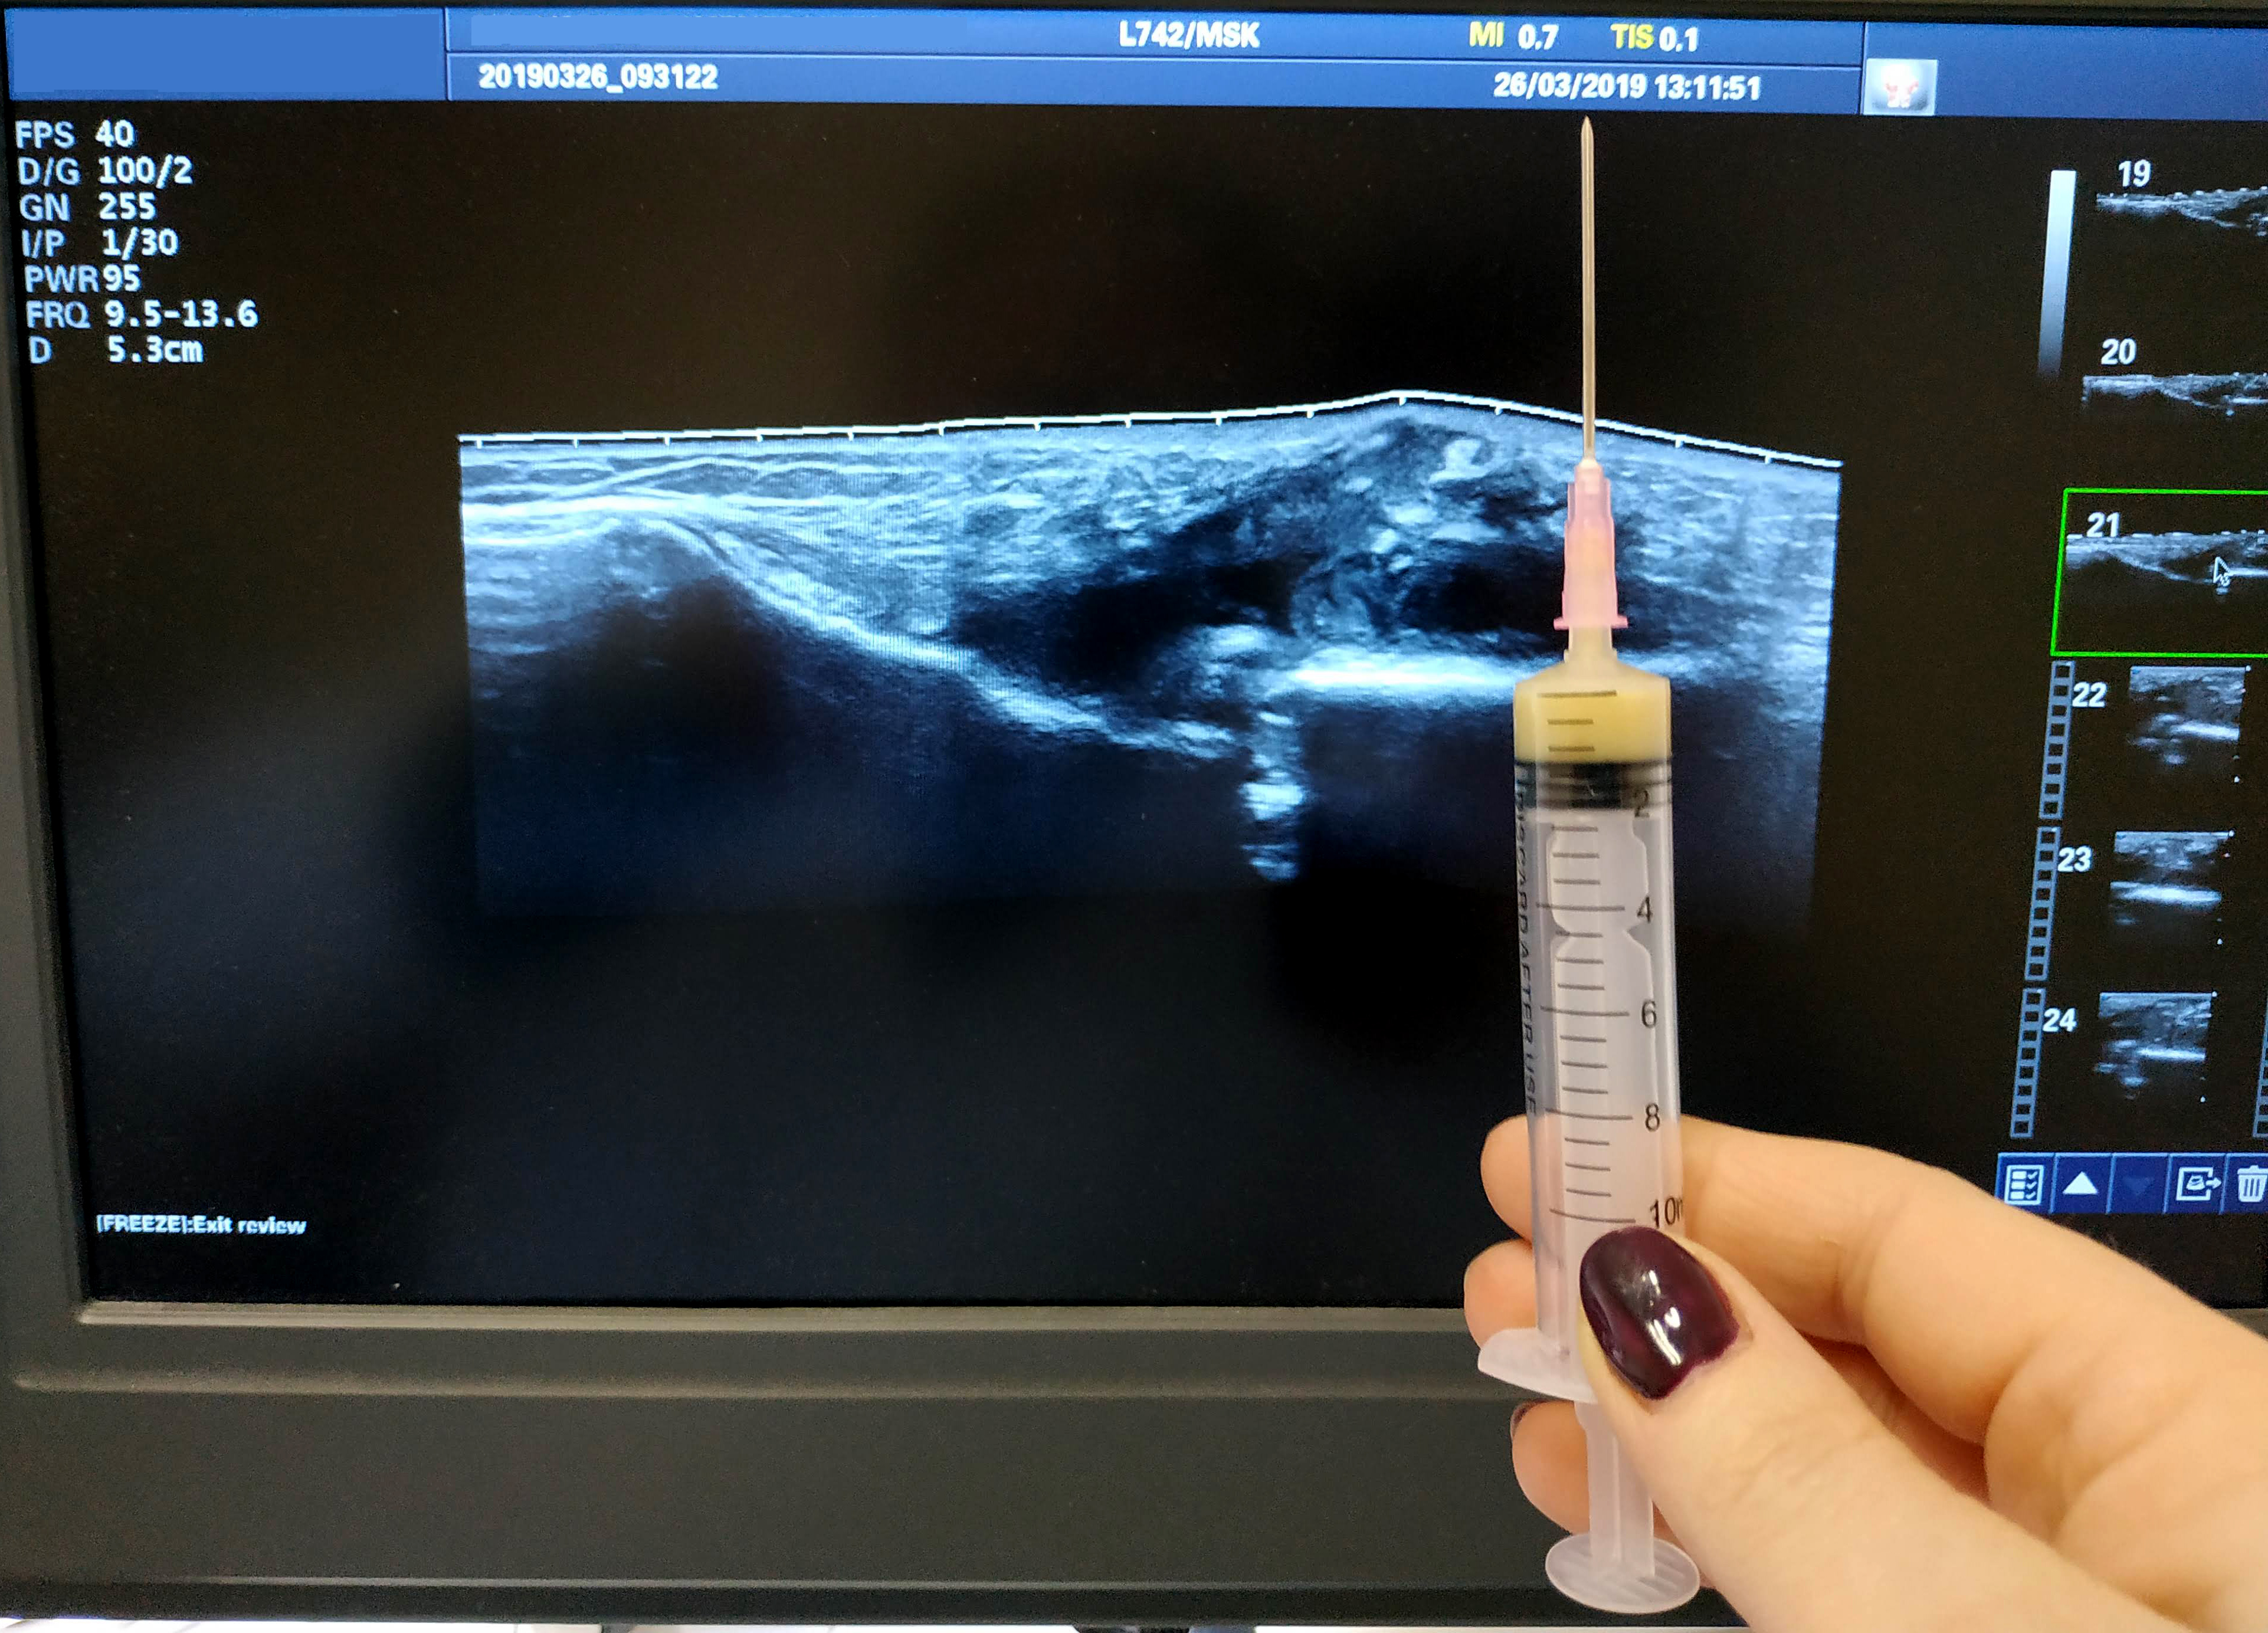

Мужчина, перелом грудины.

Пункция под контролем УЗИ

IMG_20190326_12163311.jpg